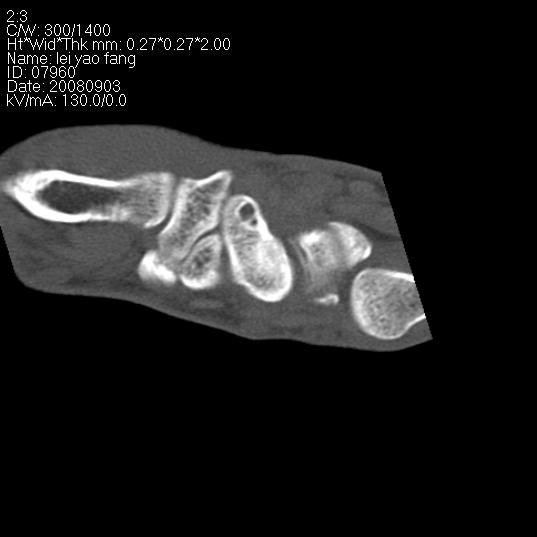

以下是引用杀毒软件在2008-9-4 17:41:00的发言:[br]考虑----舟骨囊肿